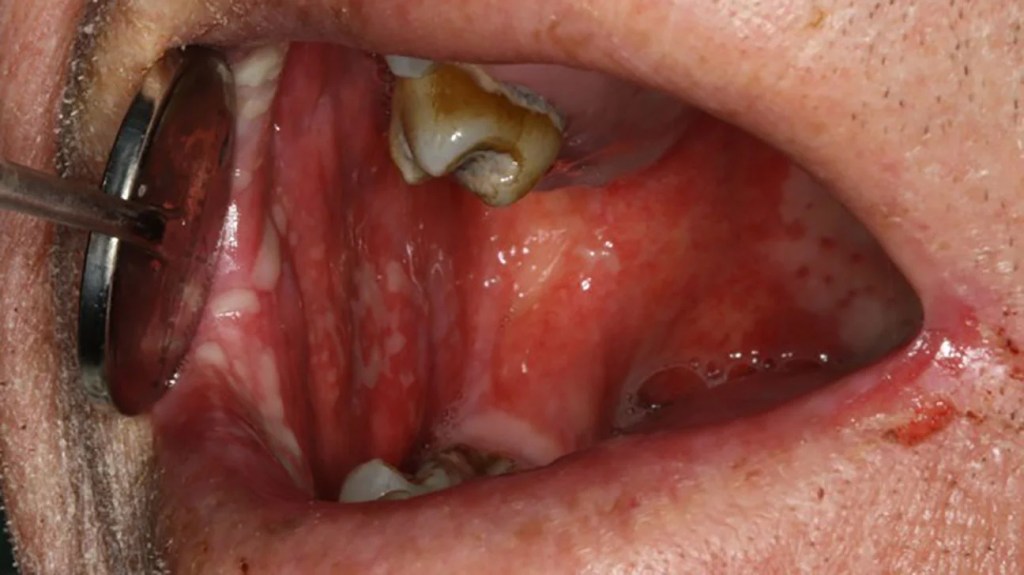

A mucosite oral é uma inflamação aguda da mucosa bucal, geralmente associada a efeitos adversos do tratamento antineoplásico, como a quimioterapia citotóxica e a radioterapia, especialmente quando direcionada à região da cabeça e pescoço.

Trata-se de uma condição dolorosa e debilitante que compromete as funções orais básicas, como mastigação, deglutição e fonação.

A patogênese da mucosite envolve uma cascata de eventos biológicos iniciada pela destruição celular epitelial, seguida por inflamação, ulceração e colonização microbiana secundária.

O quadro evolui em cinco estágios distintos: inicia-se com uma sensação de queimação, seguida por eritema, ulceração, dor intensa e, em alguns casos, formação de pseudomembranas.